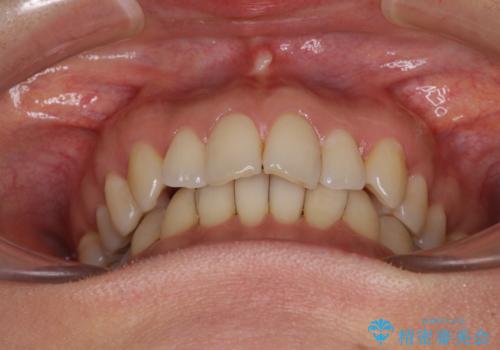

矯正治療の後戻り インビザライン・ライトによる矯正治療

- 矯正治療の後戻りを気にして来院された患者様です。

後戻りは軽微であったので、インビザライン・ライトにより矯正治療を行うこととしました。

インビザライン・ライトは提供されるマウスピースの数に制限があり、通常のタイプよりもマウスピース提供期間が短くなっている一方、安価に治療を行うことができるプランです。

治療のゴールも変更できないため、軽微な歯列不正や、後戻り改善などに適しています。